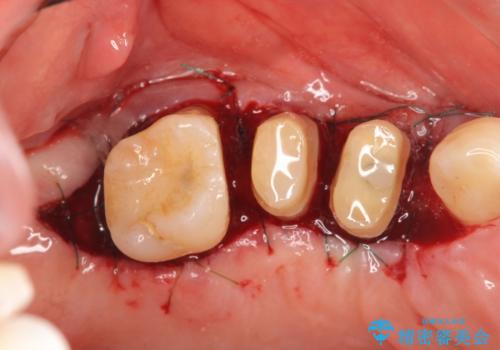

検査の結果、強い歯ぎしりによる歯の周囲の骨の吸収が認められたため歯槽骨の再生・歯周ポケットの除去・力に対抗する連結補綴・補綴前処置としての小矯正を計画します。

今回連結補綴を行うにあたり、歯周病の問題を解決するために再生療法・歯周ポケット除去手術を、またより歯の神経を保存し力に対抗できる環境を整えるために小矯正を行い精度の高いメタルボンドクラウンを製作することができました。